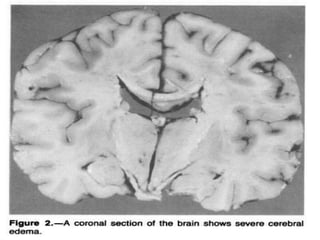

Def: Cerebral edema resulting from urea removal from

the blood more rapidly than from the CSF and brain

tissue generating a urea osmotic gradient

responsible for water moving into brain cells.

disequilibrium syndrome was developed,

shows no sulci or cisternal effacement.